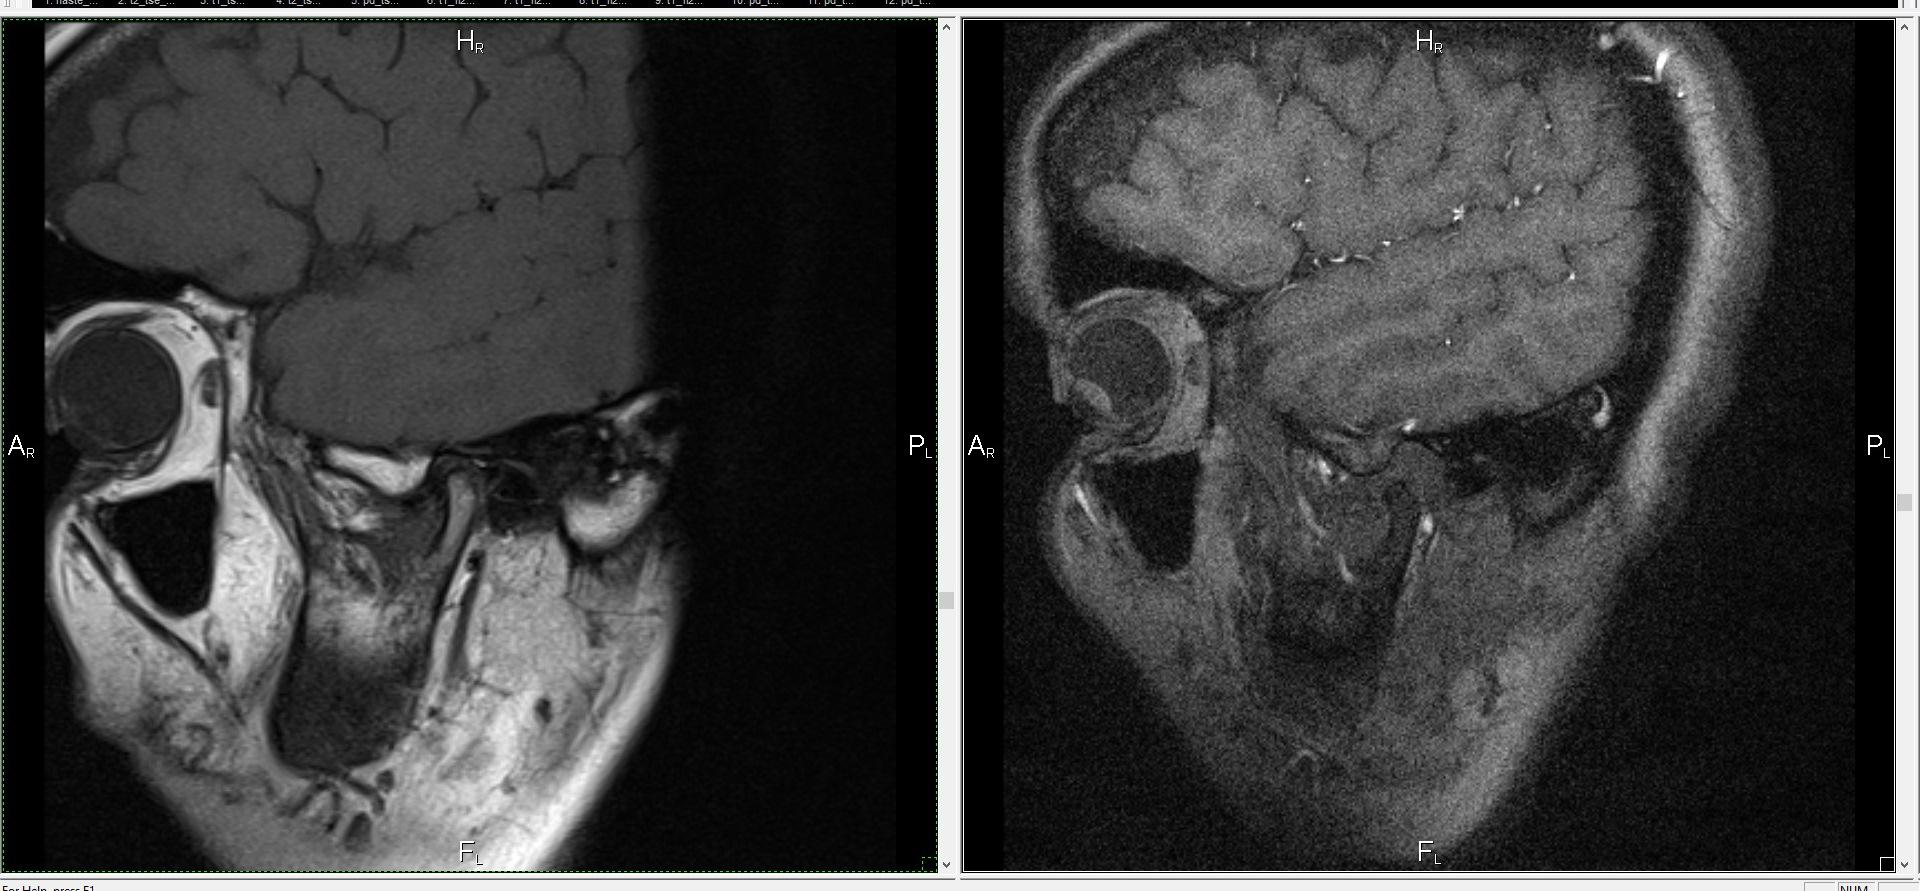

Обычный рентген или КТ показывают кости. Но височно-нижнечелюстной сустав — это не только кость. В нем есть хрящ, суставной диск, связки, мышцы. Все это — мягкие ткани. И именно они чаще всего страдают.

МРТ — единственный метод, который может четко показать все эти структуры. Без лучевой нагрузки. Это особенно важно, если речь идет о частых обследованиях или пациентах младше 18 лет.

Что показывает МРТ и как это помогает врачу

На снимках можно рассмотреть:

положение суставного диска — сместился он или нет,

состояние сустава в движении — есть ли блокировка,

воспаление или отек,

признаки артроза — если сустав начал разрушаться,

спазмы и напряжение жевательных мышц,

кисты или опухоли, если они есть.

Пациента кладут в аппарат МРТ. Процедура проходит в лежачем положении. Обычно делают два типа снимков: в покое и с открытым ртом. Это помогает оценить, как работает сустав в движении.